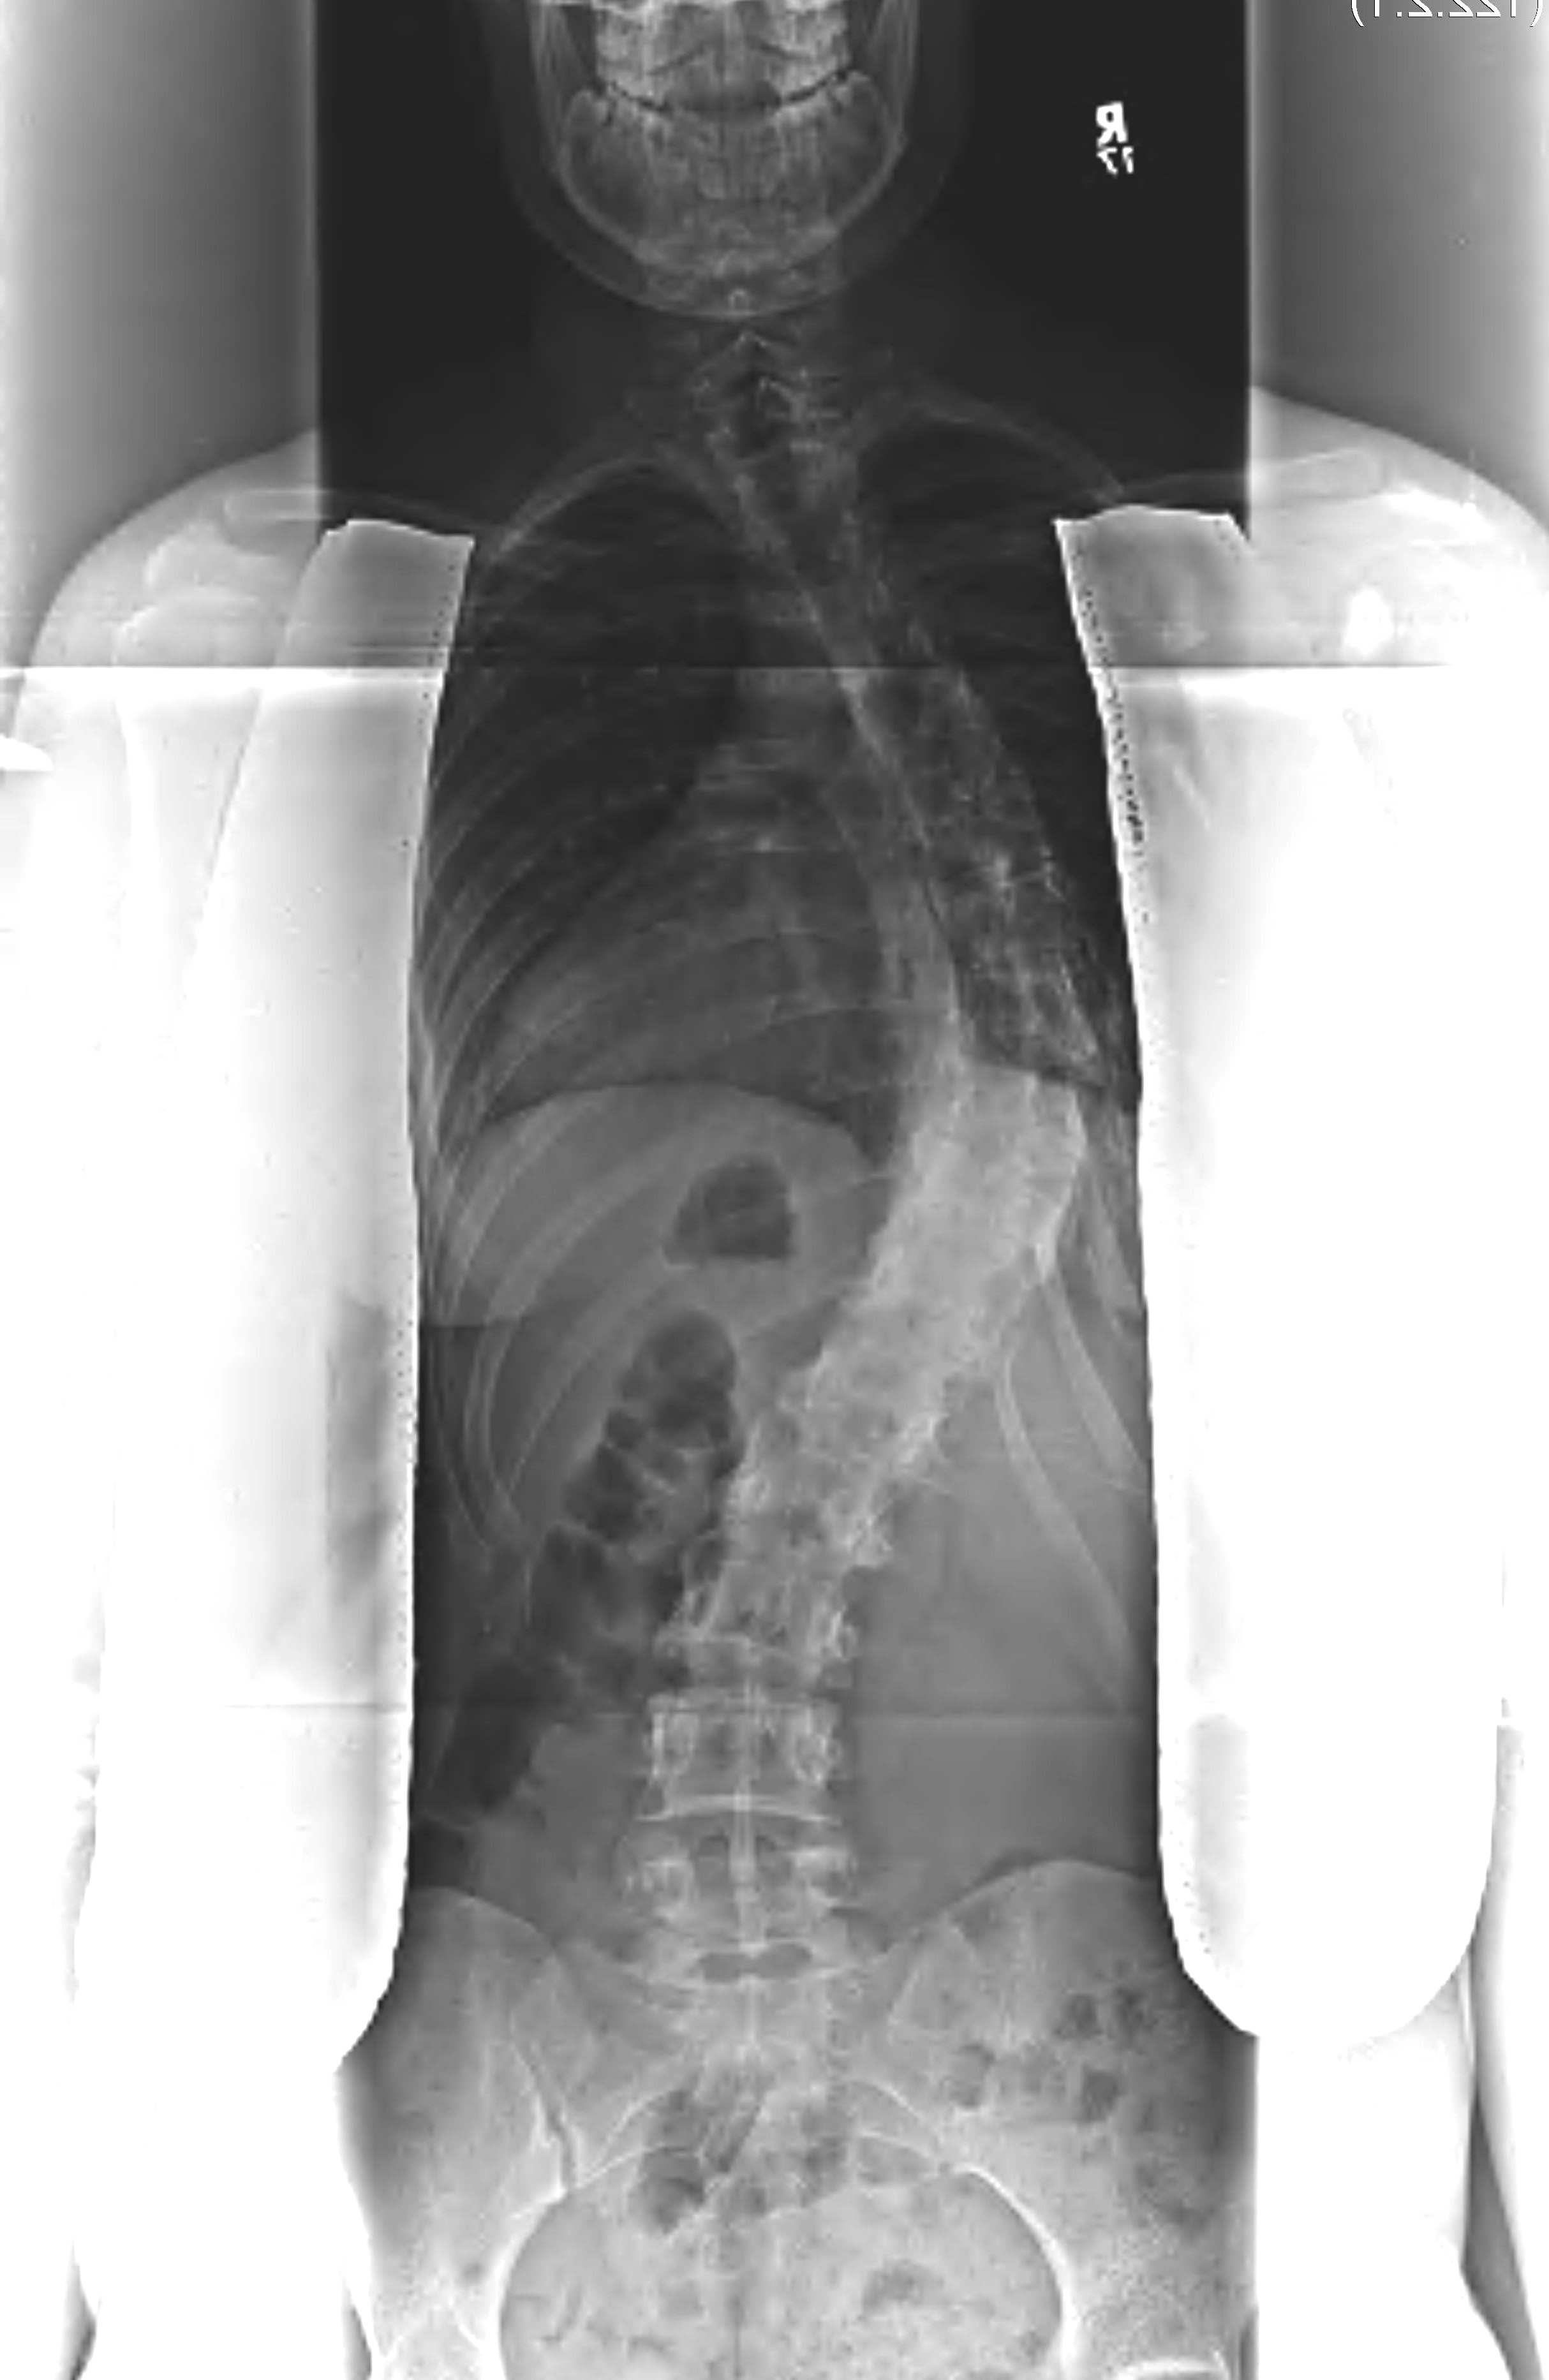

AP Film

Standing AP or PA films of whole spine including the iliac crests

- PA has less radiation to ovaries and breasts

- AP has less magnification

1. Neutral / end vertebrae

End vertebra is the last vertebra that tilts into the concavity of the curve

- when the end plates are parallel, the one furthest from the apex of the curve is the end vertebra